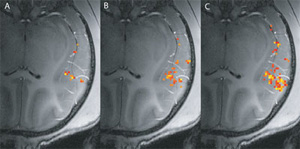

Однако новые данные, полученные немецкими исследователями из Института биологической кибернетики им. Макса Планка, показывают, что эта точка зрения не совсем верна. В действительности мультисенсорная интеграция начинается на более глубоких, сенсорных уровнях. Сотрудники Института Макса Планка пришли к такому выводу, измерив активность клеток слуховой коры приматов с помощью функционального магнитно-резонансного сканирования. Поскольку анатомическое устройство первичной и вторичной зон слуховой коры достаточно хорошо известно, ученые смогли делать свои измерения с высокой точностью. Точность была особенно важна, поскольку исследуемые области в диаметре не превышали 2-3 мм.

Результаты ФМР-сканирования показывают, что активность слухового центра, вызываемая звуковым сигналом, повышается, когда к звуковому воздействию добавляется еще и тактильная стимуляция руки. Более того, внутри слуховой коры ученые обнаружили участки, которые гораздо сильнее реагируют на импульсы, одновременно приходящие от разных органов чувств, нежели на одиночные раздражители, а это — один из основных признаков наличия мультимодальной интеграции. Также было установлено, что эта интеграция происходит во вторичной зоне слуховой коры, говорится в пресс-релизе института.